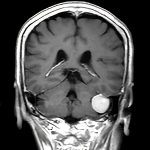

左後頭頂葉腫瘤

頭蓋内腫瘍摘出術

No.’21_62 手術前2

No.’21_62 摘出 前